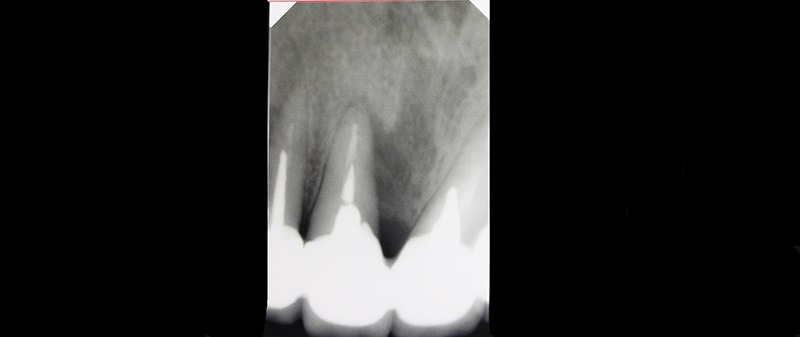

В медиальной области 11-го зуба пациентки была резорбция кости. Для лечения была проведена пародонтальная операция:

1.сглаживание поверхности корня;

2.добавление костной ткани;

3.установка мембраны.